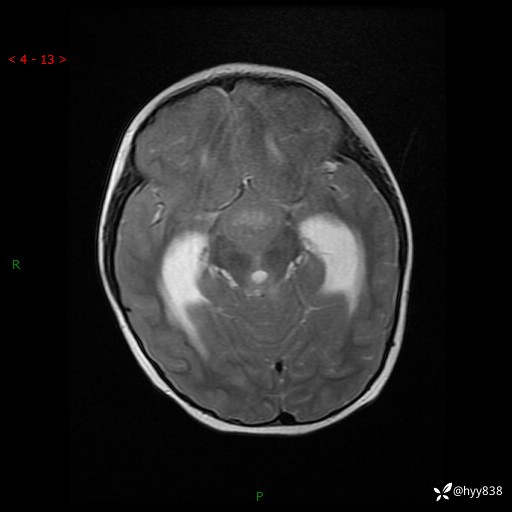

理解“经典”,从经典病例开始,3岁小女孩,行走不稳2个月,加重1个月--结果公布

性别:女

年龄:3岁

简要病史:发现行走不稳2个月,加重1个月

颅脑MRI平扫+增强

三脑室、四脑室多发病变,如何分析?

髓母细胞瘤 (13)